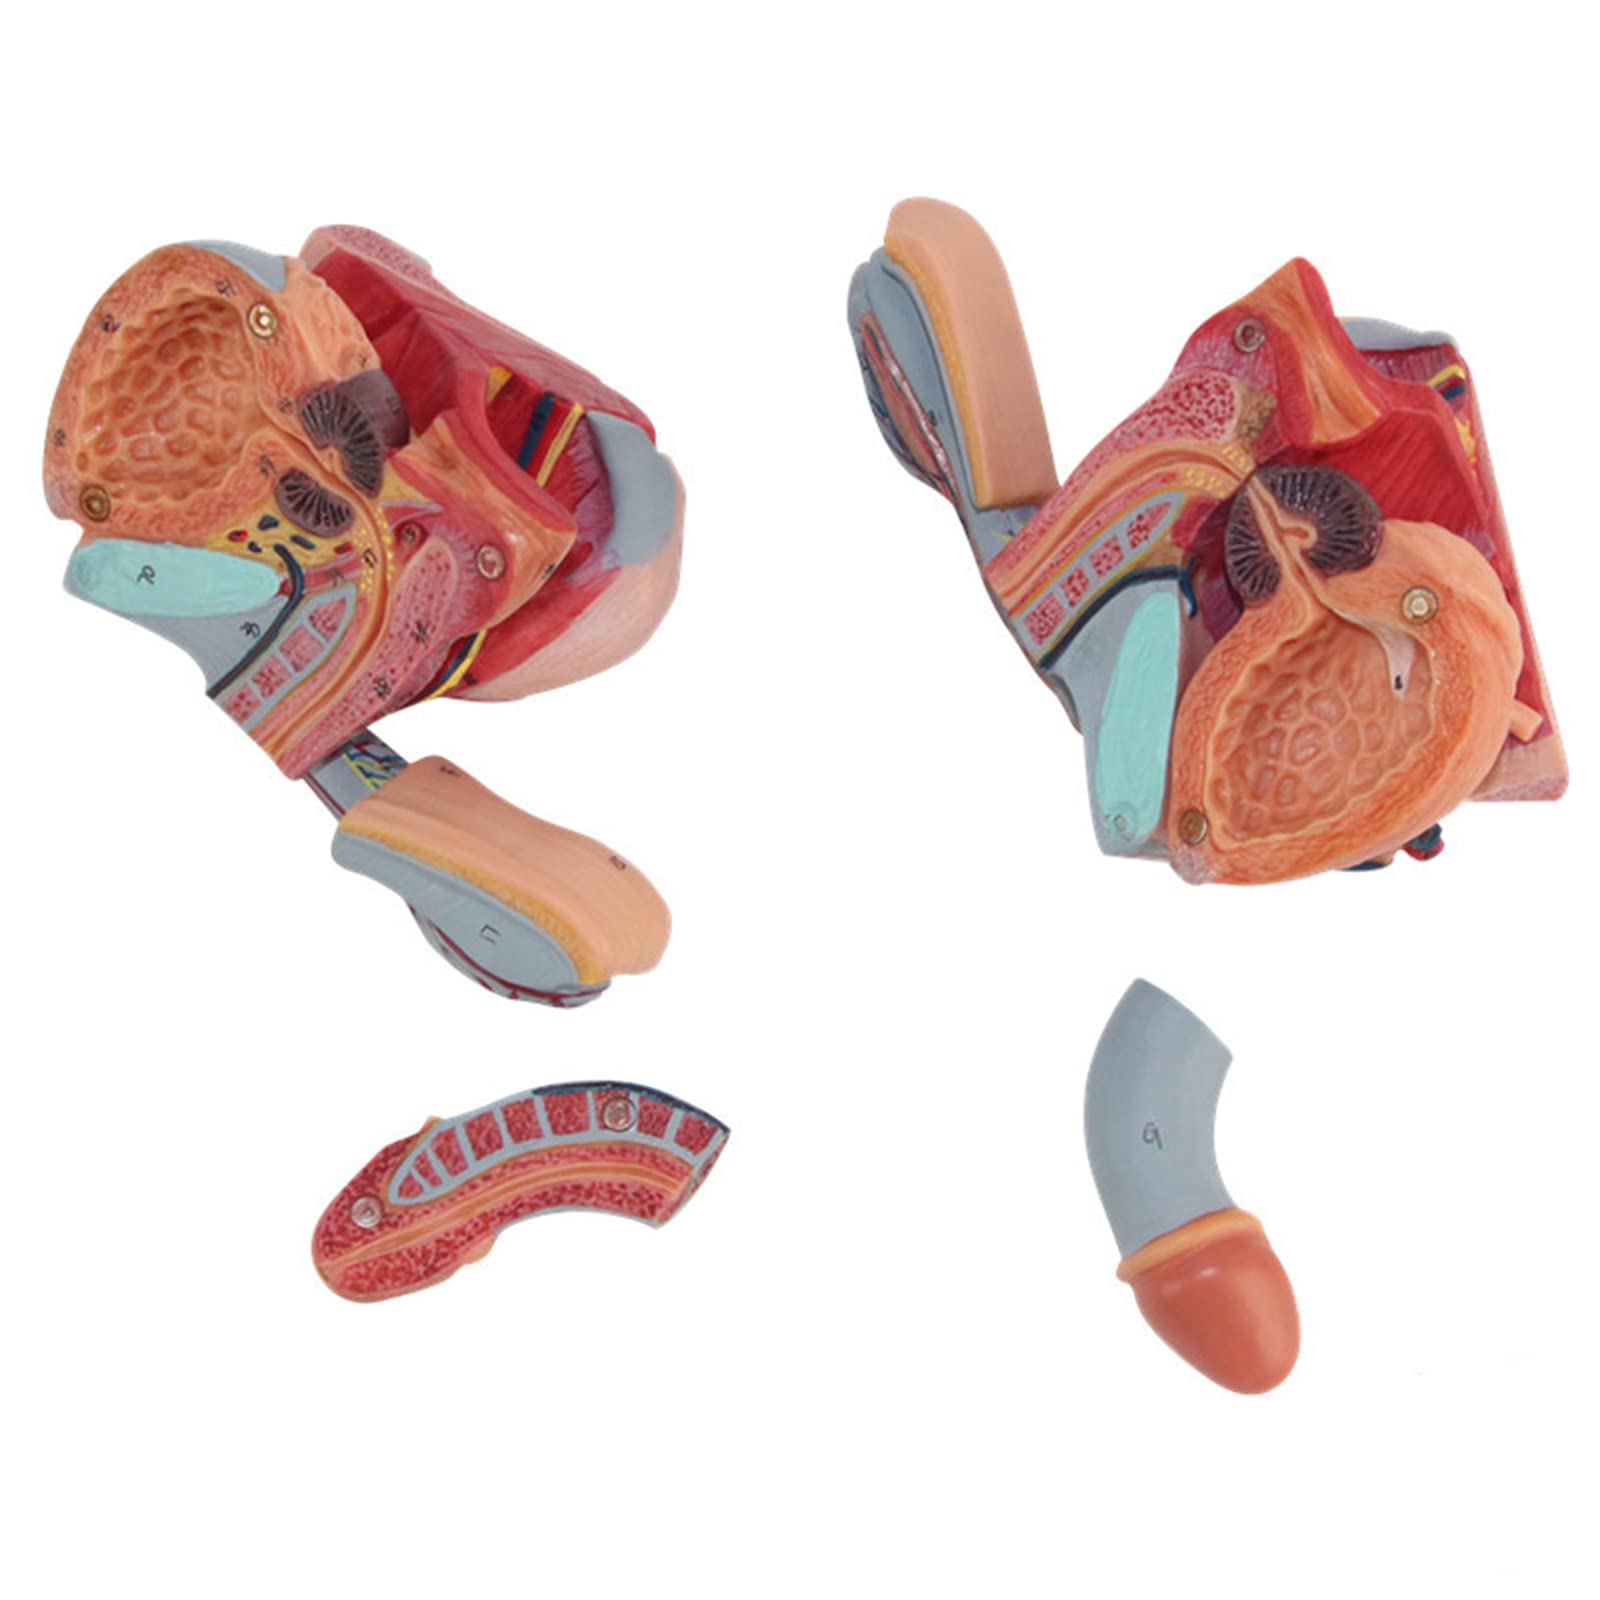

The Male Reproductive Model is a meticulously crafted anatomical aid featuring five detailed parts, including male genital organs and bladder sections. Made from durable, eco-friendly PVC, this model is designed for educational excellence, making it an ideal tool for schools and hospitals to enhance understanding of human anatomy.